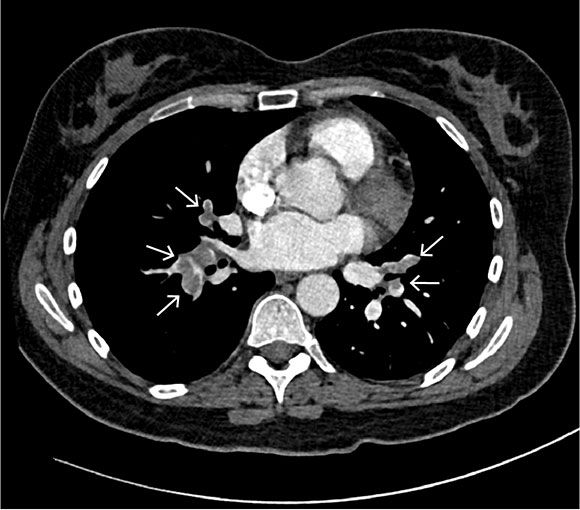

The transoesophageal echocardiogram showed patent foramen ovale with a tunnel length of 10 mm and an opening of 5 mm (Figure 3a), and a hypermobile atrial septum. Spontaneous right-to-left shunt of arterial emboli was observed using colour Doppler (Figure 3b).

The transoesophageal echocardiogram findings supported the suspicion of paradoxical embolisation with right-to-left shunt of atrial thrombus. Patent foramen ovale is usually verified by peripherally injected agitated saline and the Valsalva manoeuvre. Increased venous return to the right atrium would then cause a temporary increase in atrial pressure, which can lead to right-to-left atrial passage of microbubbles (Figure 3c).